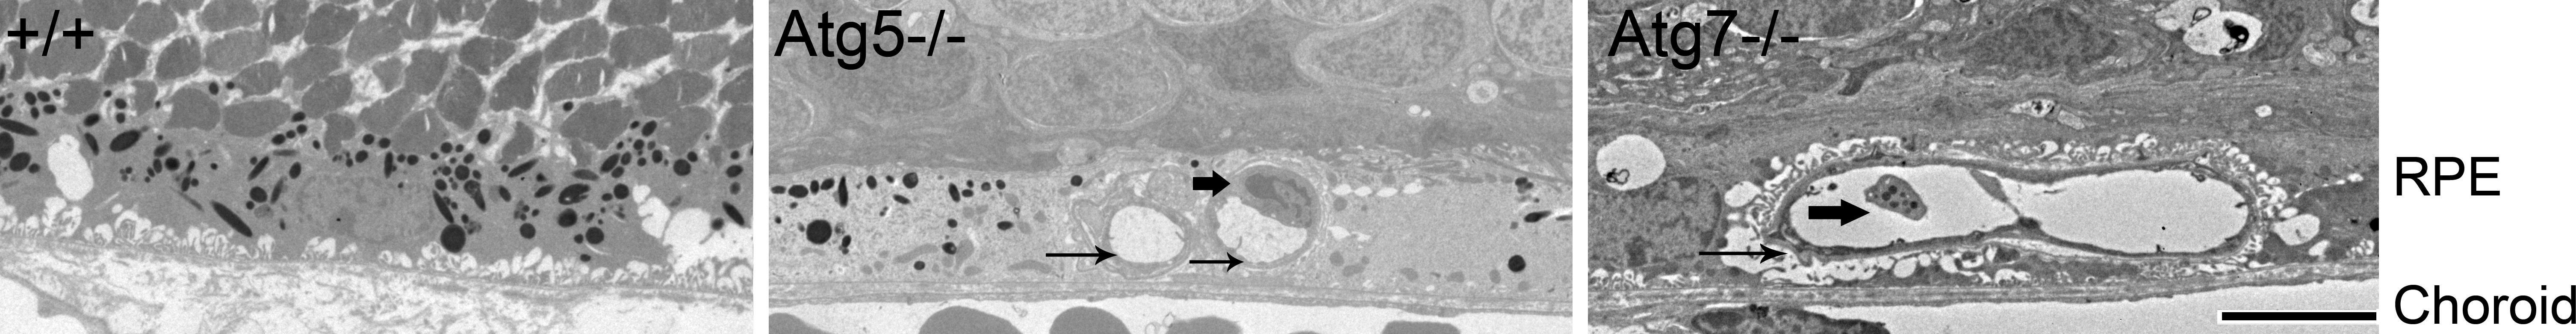

Figure 9. CNV in aged Atg5ΔRPE and Atg7ΔRPE mice. Representative electronic micrographs showing the RPE area of 17-month-old wild-type (+/+), Atg5ΔRPE (Atg5−/−), and Atg7ΔRPE (Atg7−/−) mice. Note the blood vessels (thin arrows) in the RPE layer of the Atg5ΔRPE or Atg7ΔRPE mice. Thick arrow indicates a capillary endothelial cell (Atg5−/−) or a platelet (Atg7−/−). Scale bar = 5 µm.